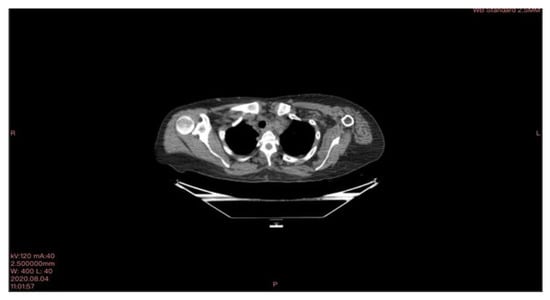

In March 2020, a 35-year-old patient arrived at our department with the results of a recently performed positive biopsy. For this reason, a CT scan of the chest, abdomen, and pelvis with means of contrast was performed in our department. CT examination confirmed the presence of several mediastinal lymph nodes. An anterior mediastinal lymph node with a diameter of (39 × 26 mm), a para-aortic lymph node with a diameter of (35 × 25 mm), a lymph node of the aorta-pulmonary window with a diameter of (30 × 20 mm) as well as several lymph nodes with diameters ranging from (27 × 16 mm) to (23 × 20 mm). Focal pleural thickening of 10 mm was confirmed at the posterior right lower lobe (peri-vertebral) (see Figure 1). For these reasons, it was decided to subject the patient to a cryosurgery intervention procedure as described above.

Figure 1. CT scan image executed.